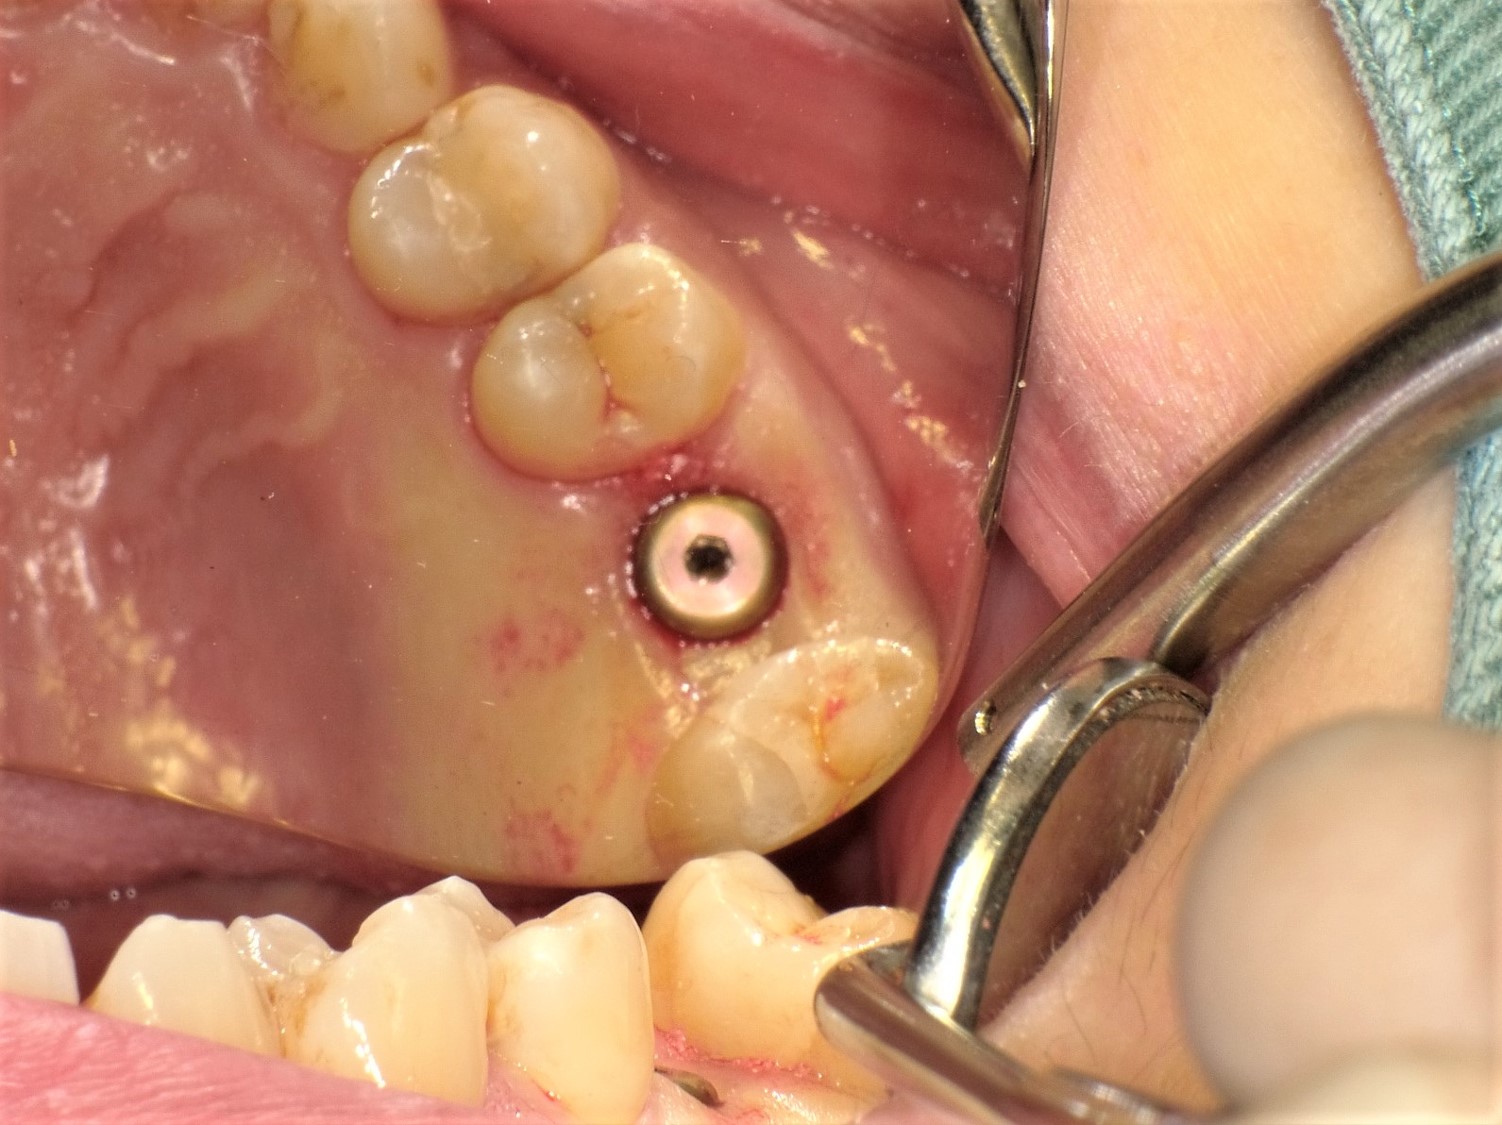

左側上顎第1大臼歯(#26) 歯牙破折症例

(40歳代 女性)

右側上顎第1大臼歯(#16) 歯根破折と根尖性歯周炎に対しての抜歯、待機埋入、ソケットリフト症例

(30歳代 女性)